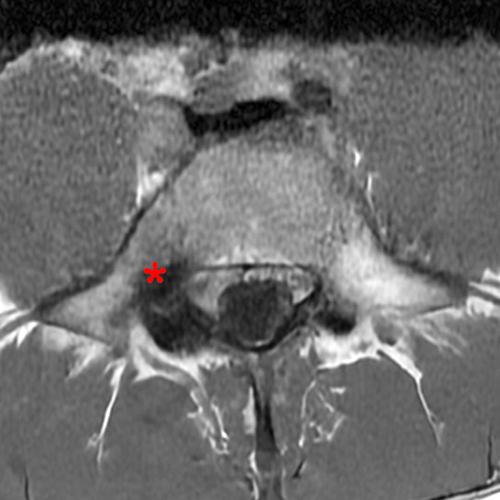

Case 2: 19-year-old male baseball player with acute onset of back pain after hitting a ball. Axial T1-weighted (2A) and T2-weighted (2B) images are provided. What are the findings? What is your diagnosis?

Case 2: T1-weighted (4A) and T2-weighted (4B) axial images show T1 hypointensity and T2 hyperintensity (arrowheads) in the left lamina of L5 adjacent to a small hypointense line (arrows) which traverses the lamina.

Case 2: Acute left-sided laminolysis